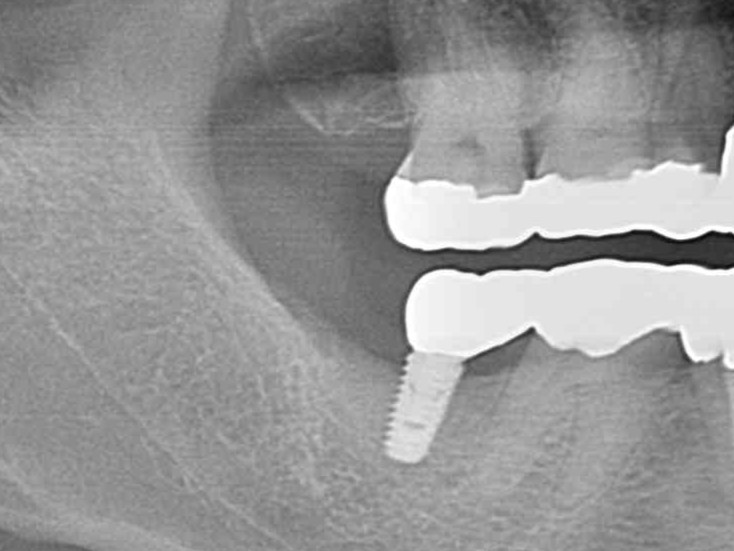

本数に関わらず手術料5.5万円(税込)歯型をとり、

一旦仮の土台が入ります。本物の土台を入れ、もう一度歯型をとります。

歯が入ります。

※1次手術の時、骨の移植が必要な場合がありますが加算料金はありません。

※2次手術の時、歯肉の移植手術が必要な場合がありますが加算料金はありません。